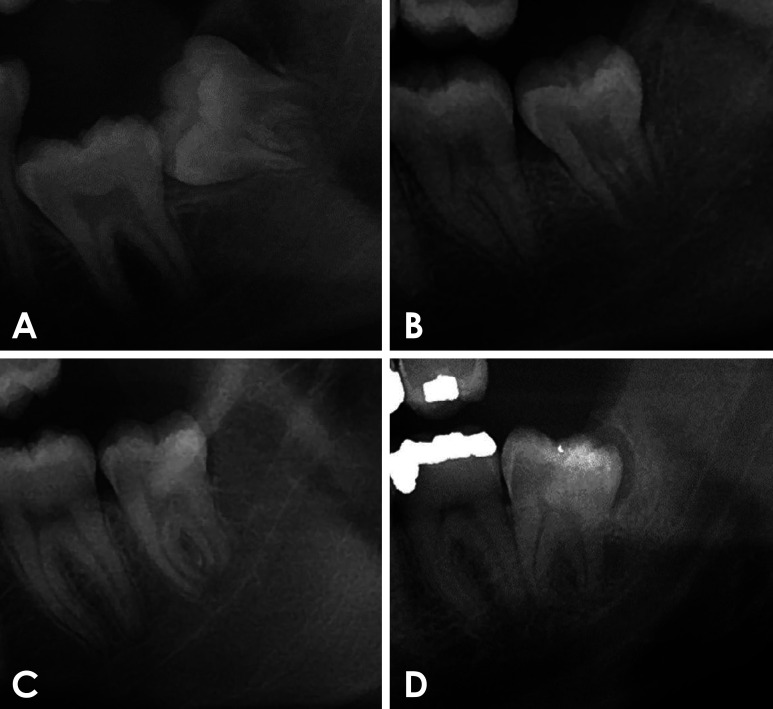

Abstract Image